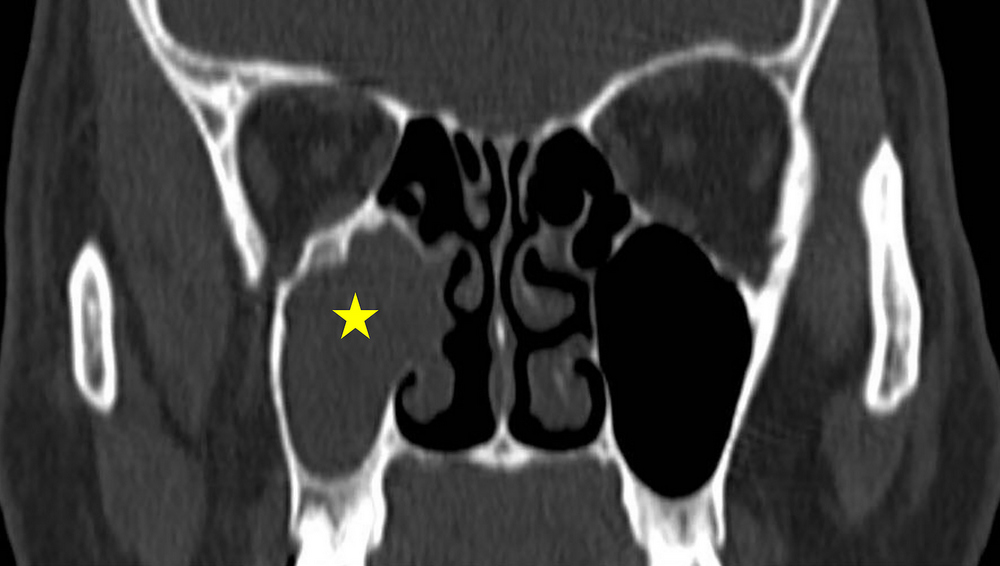

Ứng dụng đường mổ nội soi cải tiến quanh xương lệ trong bệnh lý u nhú đảo ngược ở xoang hàm

Vừa qua, Khoa Tai Mũi Họng-Mắt-Răng Hàm Mặt (TMH-M-RHM), Bệnh viện Trường Đại học Y-Dược Huế đã lần đầu tiên thực hiện kĩ thuật mổ nội soi với...